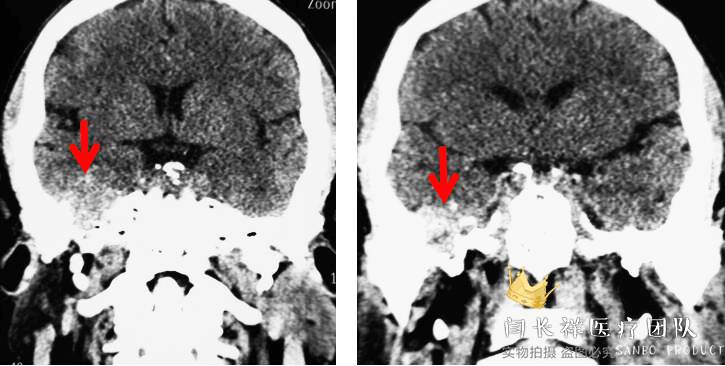

术前冠位CT示右侧中颅窝、颞下窝、翼腭窝占位,病灶呈稍高密度。

中颅窝-颞下窝占位